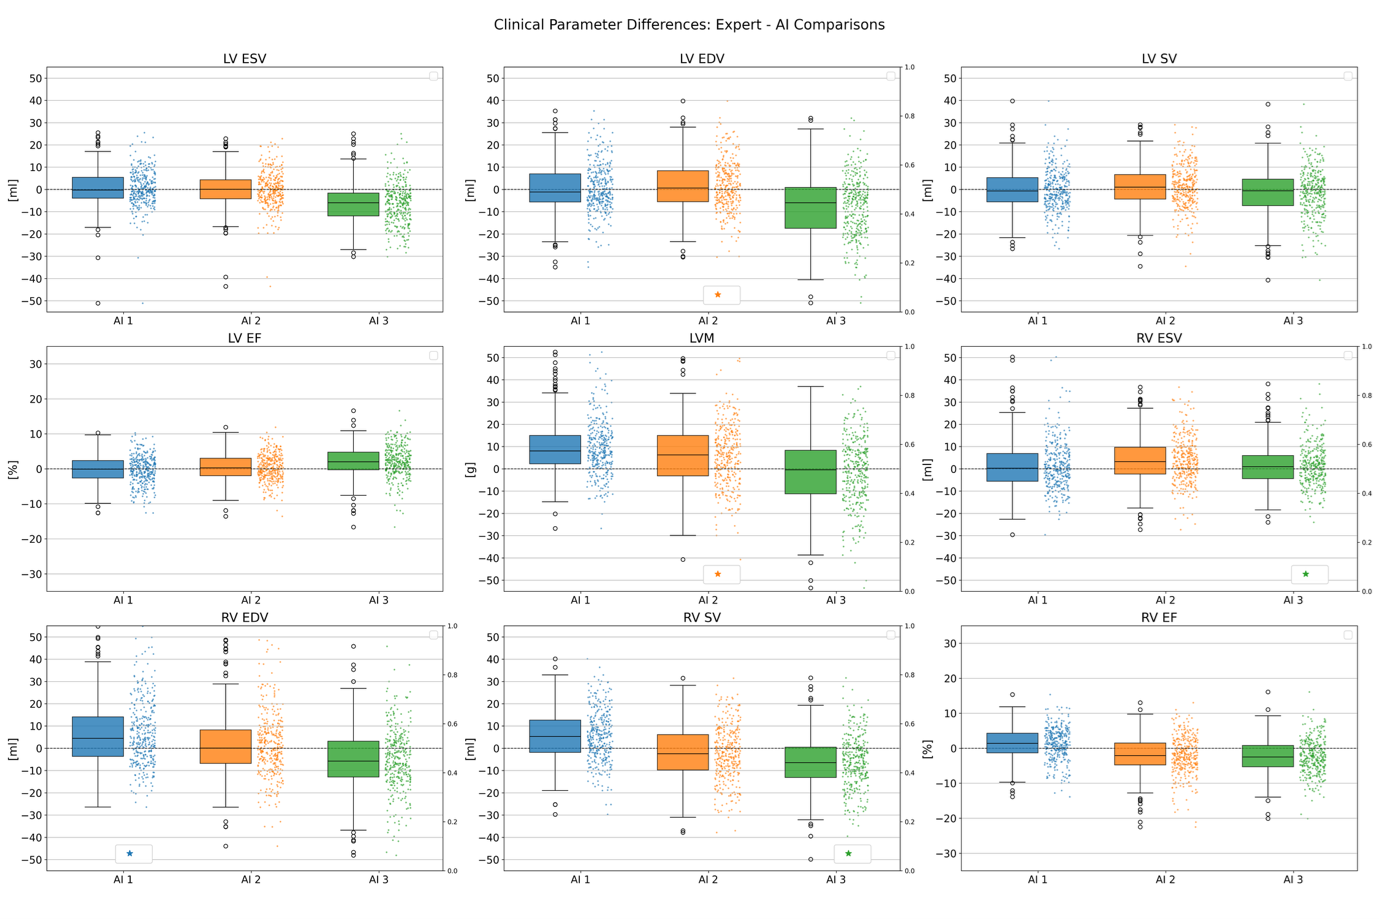

Results: Clinical parameter differences are shown in Fig. 1. For all AIs, absolute (abs.) mean differences (Δ) were low for volumes (< 10ml) and LVM (< 10g); function parameters revealed abs. ΔLVSV< 3ml, abs. ΔRVSV< 7ml, and abs. ΔLV/RVEF< 3%. Nonetheless, AIs showed individual biases: AI1 and AI2 overestimated LVM (AI1: Δ+9.4g, AI2: Δ+6g) and RV volumes (AI1 ΔEDV: +6.8ml, AI2 ΔESV: +3.9ml), while AI3 underestimated LV volumes (ΔESV: -6.4ml, ΔEDV: -7.8ml) and ΔRVEDV by -6.6ml. Segmentation decision analysis (Table 1) revealed that AI1 and AI2 contoured too many basal slices (e.g. AI1 LV Myo FPR: 17%, AI2 LV Endo FPR: 12.5%) while AI3 overlooked basal slices (e.g. AI3 LV Endo FNR: 40.5%). Basal slice differences had the largest impacts (abs. Δarea 1.7cm² – 3.9cm²). Midventricular slices had negligible decision differences (FPR< 1%, FNR=0), high Dice averages (Dice >80%), and small abs. Δarea (< 1,7cm², except AI2 RV Endo: 2.5cm²). Apical slices were less reproducible: all AIs overlooked apical slices (FNR >15%) and showed low Dice values (< 65%), however with lower impact (abs. Δarea < 1cm²). Example segmentations are provided in Fig. 2.

Conclusion: Across a diverse cohort, industry-provided AI post-processing solutions demonstrated good segmentation performance. However, relevant differences between AI solutions led to different biases for clinical parameters. Differences are caused by segmentation strategies, and inclusion choices for basal and apical slices, consistent with the surrounding literature (4). All AIs segmented midventricular slices accurately and may be integrated into clinical routine as support tools to amplify efficiency.